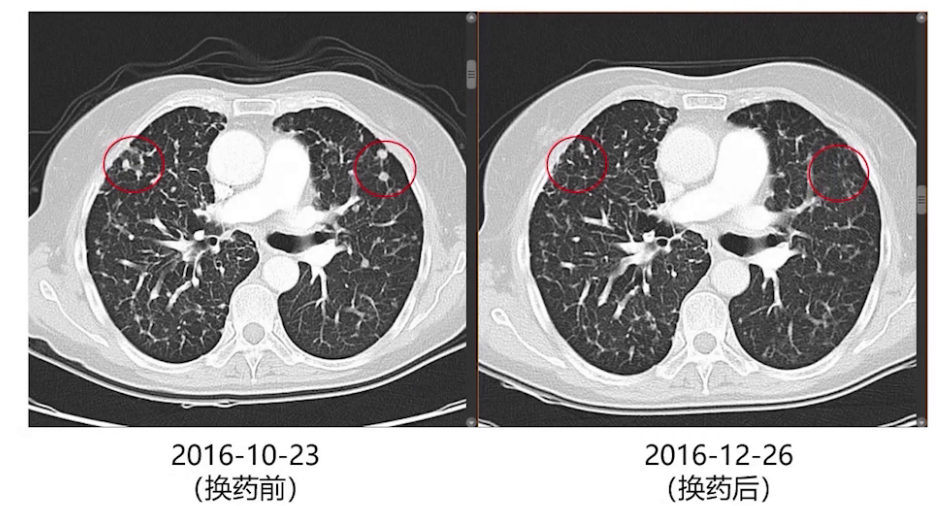

术后3个月、6个月及9个月复查,双肺结节逐渐增大,考虑厄洛替尼耐药,2016年10月改服奥西替尼。两个月后影像复查,双肺增大的结节再次缓解。此后每2-3个月复查胸部增强CT,每半年进行一次全身检查。